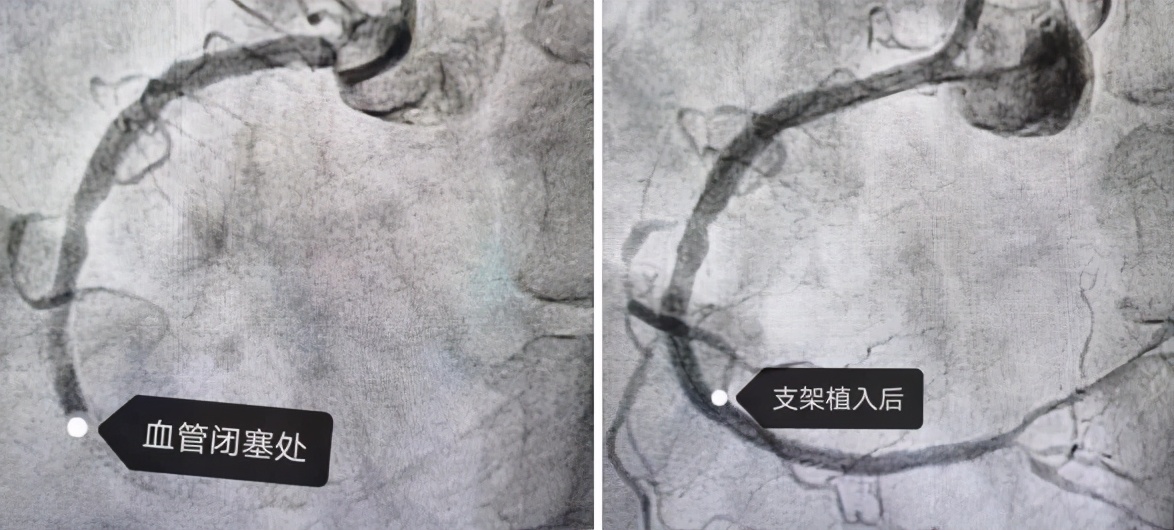

沈阳市第一人民医院心血管内三科主任医师杨新滨放弃休息时间,与介入团队及导管室多科室紧密合作,迅速行急诊冠脉造影,术中显示:右冠中段100%闭塞,局部可见血栓影,于右冠植入支架1枚,术后患者胸痛缓解,转危为安。